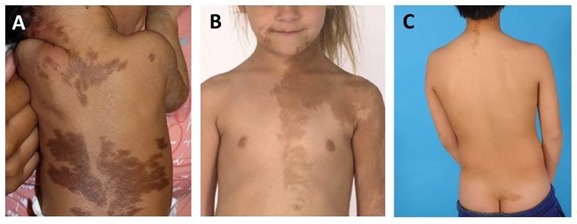

Figura 1. Lesiones cutáneas

A. Lesiones cutáneas en un recién nacido respetando la línea media del cuerpo y mostrando una distribución que refleja los patrones de la migración de las células embionarias (líneas de Blaschko).

B. Manchas “café con leche” típicas con un aspecto serrado e irregular que afectan al tórax, la cara y el brazo.

C. Manchas “café con leche” de aspecto característico en la nuca y en la hendidura glútea.